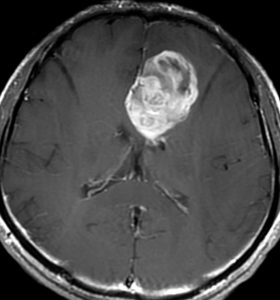

退形成性星細胞腫 グレード3の膠芽腫としての再発例

左上前頭回のびまん性グリオーマ diffuse glioma です。手術でほぼ全摘 gross total removalして54グレイの放射線治療とテモゾロマイド化学療法をしました。病理診断は,oilg 2陽性,1p/19q染色体の欠失はない退形成性乏突起星細胞腫 グレード3とされました。全体的にはグレード2であるとの病理医の意見もありましたし,当時は北大病院でもIDHの正確な分子病理診断は行われていませんでした。

5年後です。上前頭回の病巣は落ち着いていましたが,初回にはなかったはずの場所,脳梁前方に急激な再発増大を生じました。また手術で全摘出 gross total removalして,かなり絞った領域に60グレイの放射線治療とテモゾロマイド,アバスチンの投与をしました。病理診断は,IDH wild-tpye, 1p/19q non-codel, MIB 40%, ATRX positive, MGMT negativeの膠芽腫でした。

その後またしばらく寛解継続できました。